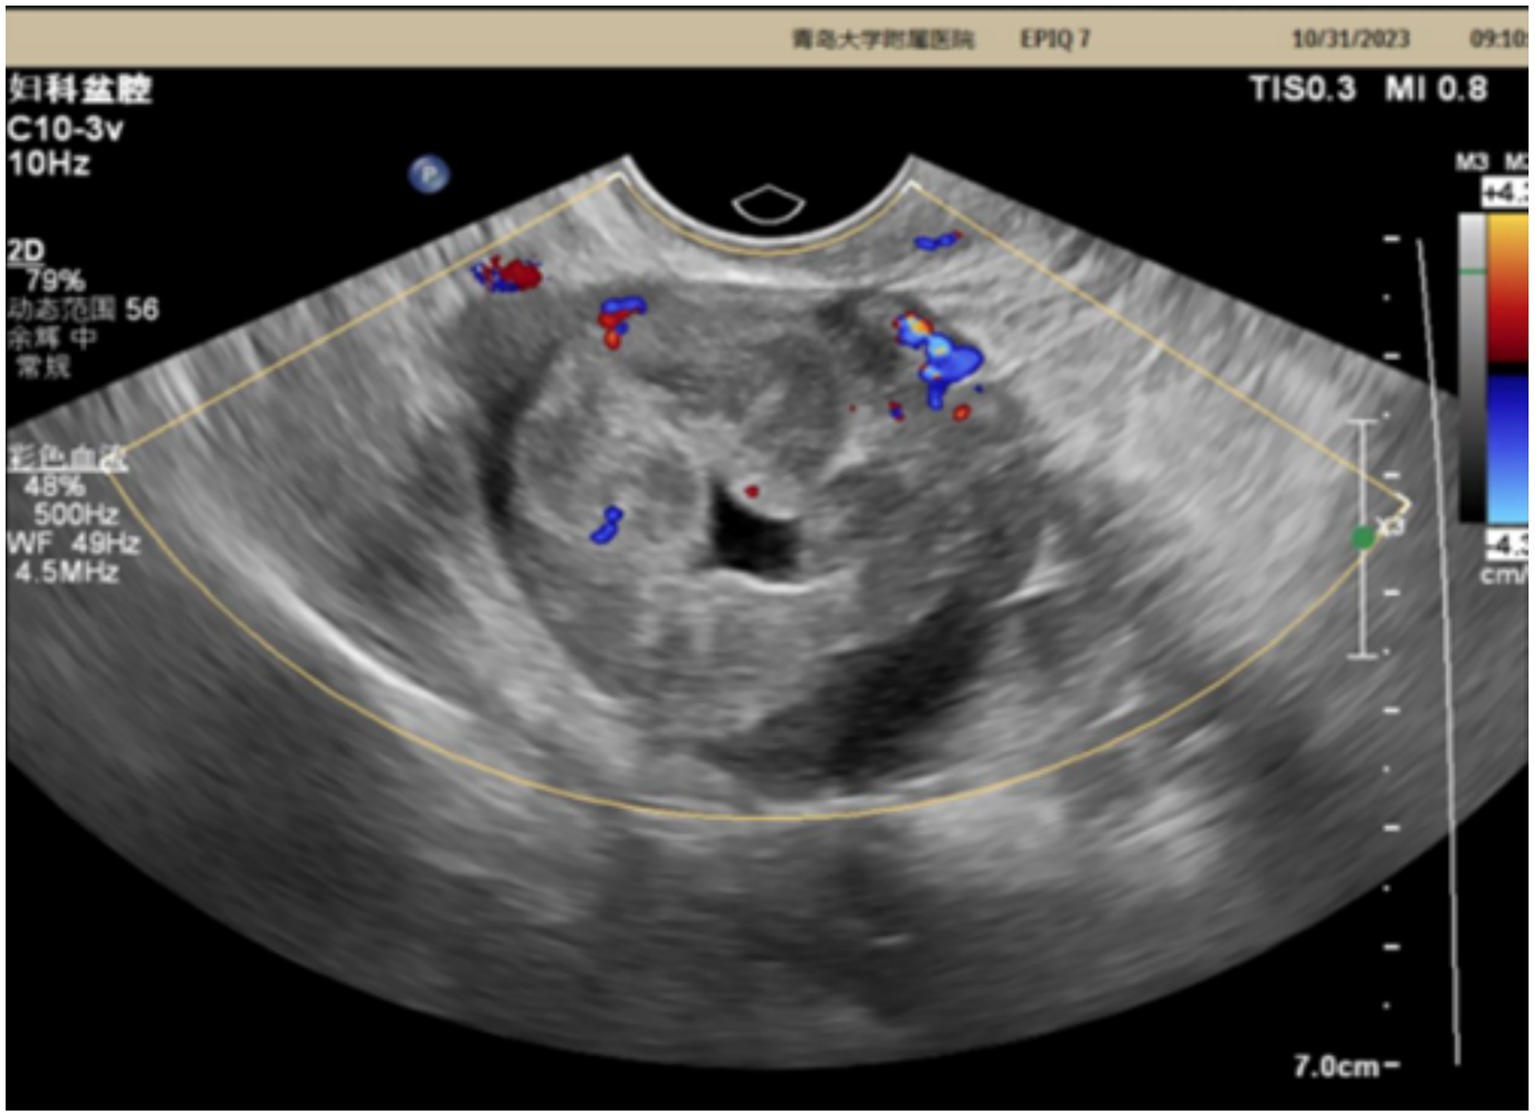

The patient is a 42-year-old married woman (G1P1) with a regular menstrual cycle of 5–6/25 days. She was admitted to the gynecology department of The Affiliated Hospital Of Qingdao University on 1 November 2023, due to her primary complaint of a “pelvic tumor found during a physical examination 3 years ago.” During this examination, an ultrasound revealed a right ovarian cyst measuring 3 cm in diameter. After admission, a follow-up ultrasound showed the following: an uneven echo mass in the right uterine adnexa, measuring 5.1 × 4.0 × 4.3 cm, an irregular echoless area in the center, and a striped blood flow signal in the center (Figure 1). Upon gynecological examination, a 5 cm palpable solid mass with good motion and no tenderness was identified in the right adnexal area, and no palpable abnormality was found in the left adnexal area. Sex hormone FSH:4.57 IU/L; LH:2.85 IU/L; PRL:311.54 mIU/L; E2:290.08 pmol/L; and AMH 1.80 ng/mL; thyroid hormones: FT3:4.00 pmol/L; FT4:14.10 pmol/L; and TSH:2.530 mIU/L; and tumor markers: CA125: 16.18 U/mL; CA199: 23.65 U/mL; CA153: 6.07 U/mL; AFP: 2.01 ng/mL; CEA: 3.29 ng/mL; and HE4: 54.94 pmol/L. The preoperative diagnosis indicated a right ovarian cyst with the potential for malignancy. Later, an elective laparoscopic oophorectomy of the right ovary was performed. During the procedure, solid masses of approximately 5 cm in diameter were found in the right ovary, which were hard in texture. No obvious abnormalities were found in the appearance of both fallopian tubes and the left ovary, and no obvious ascites was observed in the abdominal cavity. No enlarged lymph nodes were palpated in the pelvic cavity. The right pelvic funnel ligament, the root of the right fallopian tube, and the proper ligament of the right ovary were disconnected, and the right adnexa along the right mesosalpinx and the posterior leaf of the right broad ligament were removed. The right adnexa was placed into a specimen bag and removed through the puncture site. The tumor did not rupture during surgery. The surgery lasted 1 h, with an estimated blood loss of approximately 10 mL, and the patient had no significant perioperative complications. Considering that this was a borderline malignancy, the ovarian surface remained intact and no tumor tissue was observed; hence, peritoneal washings were not retained. Gross appearance: the right fallopian tube was 5.5 cm long with a maximum diameter of 0.8 cm, and the fimbrial end was visible. The right ovary was cystic, measuring 5 × 4 × 2.7 cm, with a gray-yellow solid cut surface. Observed under the microscope: Trabecular and insular carcinoid component and colloid-filled thyroid follicles without cytological atypia. No capsular invasion and necrosis, and mitotic count < 1/10 high-power field (HPF). Intraoperative freezing: The right ovary was considered carcinoid, and a small amount of thyroid follicular epithelium was found, which was initially misinterpreted as carcinoid tissue within the ovary. Postoperative pathology: (right ovary) consistent with struma carcinoid. Immunohistochemistry (IHC): CKpan(+), CD56(+), CK7(−), CK19(+), Syn(+), insulinoma-associated protein 1 (INSM1; +), somatostatin receptor type 2 (SSTR2; 3+), TTF-1(−), Pax-8(+), and Ki-67(1%; +) (Figure 2). IHC was mainly performed on the carcinoid areas, and the differentiated thyroid regions were not subjected to detailed IHC, or the proportion of differentiated thyroid tissue sampled was small. We believe this may explain why TTF-1 was negative and synaptophysin (Syn) was positive on slide review. The diagnosis was confirmed by two gynecological pathologists and discussed within the department. External consultation was not required, but is noted as advisable for rare mixed lesions. Postoperative diagnosis: right ovarian strumal carcinoid (stage IA). Patients were closely followed at 1, 3, 6, and 12 months postsurgery. Ultrasonography depicted that the size of both ovaries was normal, and no abnormal echo region was found. No abnormalities were found in the tumor index and thyroid and sex hormones. The patient has not yet reached 24 months postsurgery, which is one limitation of this case; follow-up should continue.

Ultrasound image displaying a grayscale pelvic scan with highlighted areas in red and blue, indicating blood flow. Text overlays with frequency and settings information are visible, along with a color scale on the right.

Figure 1. Ultrasonic image.